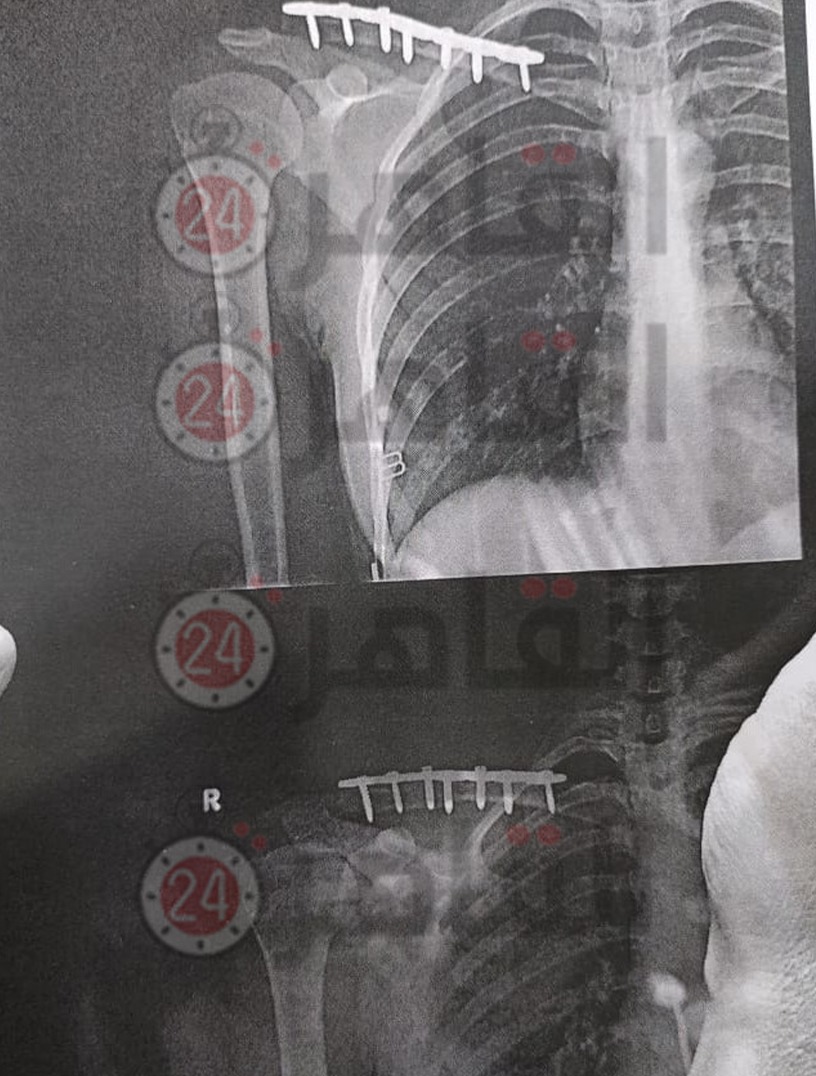

التقرير الطبي لـ جنة عليوة

وأضاف التقرير الطبي الخاص بـ جنة عليوة، أنها تعاني من سحجات متفرقة بالكتف الأيمن، والذراع الأيمن والركبة اليمنى والجانب الأيمن، وكدمة شديدة بلوح الكتف الأيمن، والحالة العامة مستقرة.

كما كشف التقرير الطبي الصادر بتاريخ 27 أبريل الماضي، إصابة جنة عليوة بكسر بعظمة الترقوة اليمنى وتحتاج لـ حامل ذراع وفترة علاج.